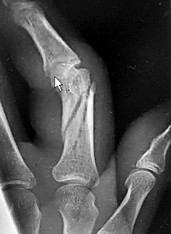

- الأشعة السينية (X-rays): هي الخطوة الأولى في تقييم الكسور، الخلوع، وتغيرات التهاب المفاصل. تساعد في تحديد مدى تدهور العظام والمسافات المفصلية. على سبيل المثال، تُظهر صور الأشعة السينية كسور السلاميات

أو كسور قاعدة العظم المشطي الخامس